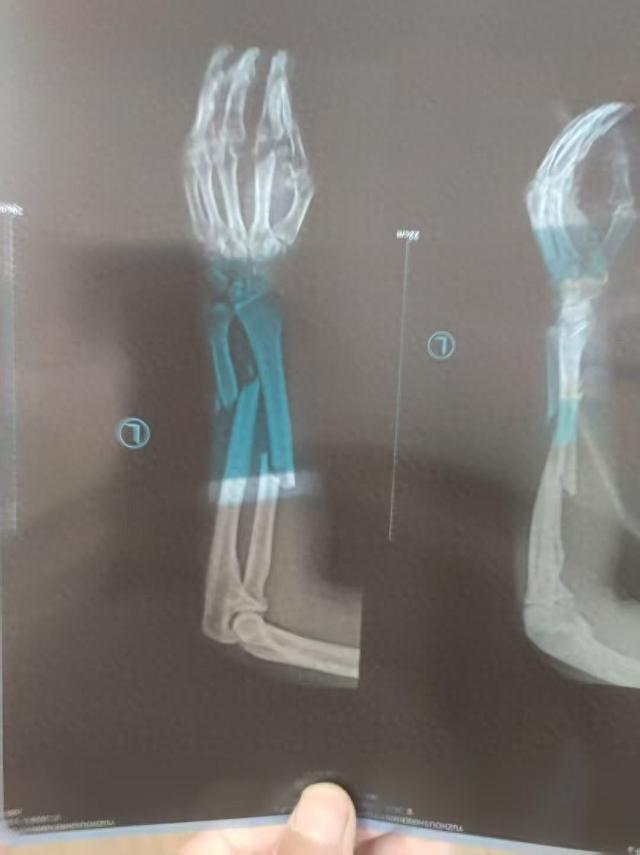

河南男子王先生在煤矿巷道中打钻施工时胳膊被钻机拧断,被鉴定为八级伤残,劳动仲裁认定企业需支付王先生工伤补助金37万余元,煤矿却迟迟不支付,法院查封了等值的800吨煤,却在拍卖前被矿上卖掉了。10月16日,华商报大风新闻以《“男子被钻机拧断胳膊,难获37万工伤补助金”:法院查封的800吨煤,拍卖前被矿方私售》为题对此事进行了报道,引起当地相关部门和涉事单位的重视。